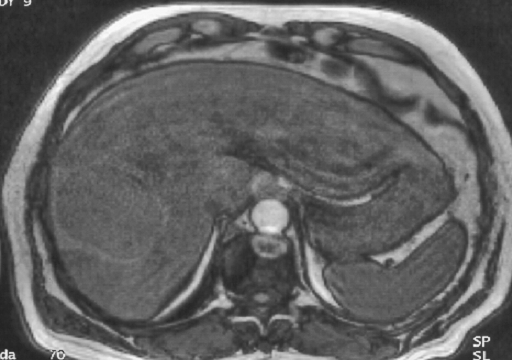

T1 Gado phase tard ive T1 Gado phase tardive

La masse est franchement hypervasculaire à la phase artérielle. La capsule se rehausse plus tardivement ainsi que la zone de nécrose.